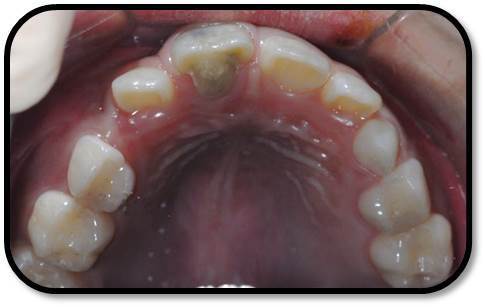

检查: 右上1牙冠略宽大,舌侧见粗大的畸形舌尖,叩痛(++),松Ⅰ°,唇侧牙龈红肿前庭沟膨隆扪痛,挤压唇侧龈缘溢脓,冷热测无反应,右侧上下1侧方颌,正中颌颌创伤。 X线:右上1发育7-8期,根管平行状,根尖孔宽大,约5-6mm宽,根尖周低密度影。髓腔根管宽大内见倒置牙影像,倒置牙可见髓腔。 余牙未见异常 6均已萌出建颌

初步诊断:右上1牙内陷根尖炎,颌创伤 治疗计划:1、口腔卫生宣教 2、右上1调合,牙髓再血管化治疗, 成年后烤瓷贴面修复 3、定期复查(1月、3月、6月--) 处置:右上1STA必兰局麻下舌侧开髓,查得两根管,一个是长扁根管,一个是牙中牙内陷盲袋形成的椭圆根管,拔根髓不成形,5.25%次氯酸钠冲洗浸泡根管5-10分钟,超声根管荡洗,反复3次,2%CR冲洗根管,隔湿干燥后,封Ca(OH)2。调合,去除咬颌创伤。 复诊:隔2周复诊,行5.25%次氯酸钠冲洗浸泡根管5-10分钟,超声根管荡洗,反复3次,2%CR冲洗根管,隔湿干燥后,封Ca(OH)2。 此后复诊每隔1周行2.5%次氯酸钠冲洗浸泡根管5-10分钟,超声根管荡洗,反复3次,2%CR+NS冲洗根管,隔湿干燥后,封Ca(OH)2。 2个月后:患牙症状消失,临床检查无阳性体征,去暂封无渗出,2.5%次氯酸钠冲洗浸泡根管5-10分钟, 2%CR+NS冲洗根管,隔湿干燥后,用无菌30#根管锉超出根尖3-4mm刺破根尖组织出血,待形成血凝块后,置MTA,GIC,冠方树脂严密充填。